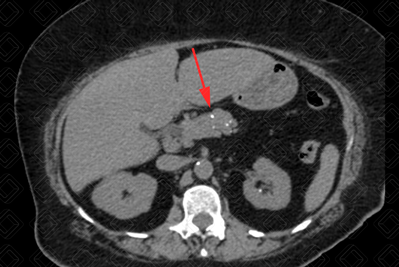

Texto alternativo para a imagem Figura 2. Créditos: Dra. Elazir Mota - Rio de Janeiro/RJ

Descrição das figuras 1 e 2: Tomografia computadorizada do abdome. Pâncreas com discreto afilamento difuso e apresentando focos de calcificação dispersos pelo parênquima pancreático (setas vermelhas).

• Tomografia computadorizada do abdome: Ducto pancreático principal dilatado (valor de referência normal até 3,5 mm), calcificações pancreáticas, redução do volume pancreático, alteração do seu contorno e surgimento de pseudocistos (figura 1);